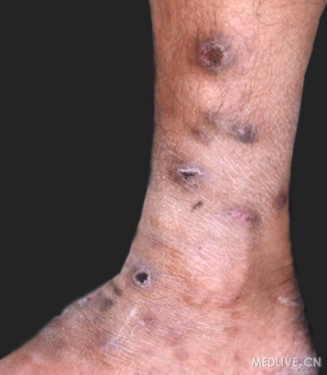

下肢孢子丝菌病-淋巴管型

下肢孢子丝菌病-淋巴管型(放大照片)